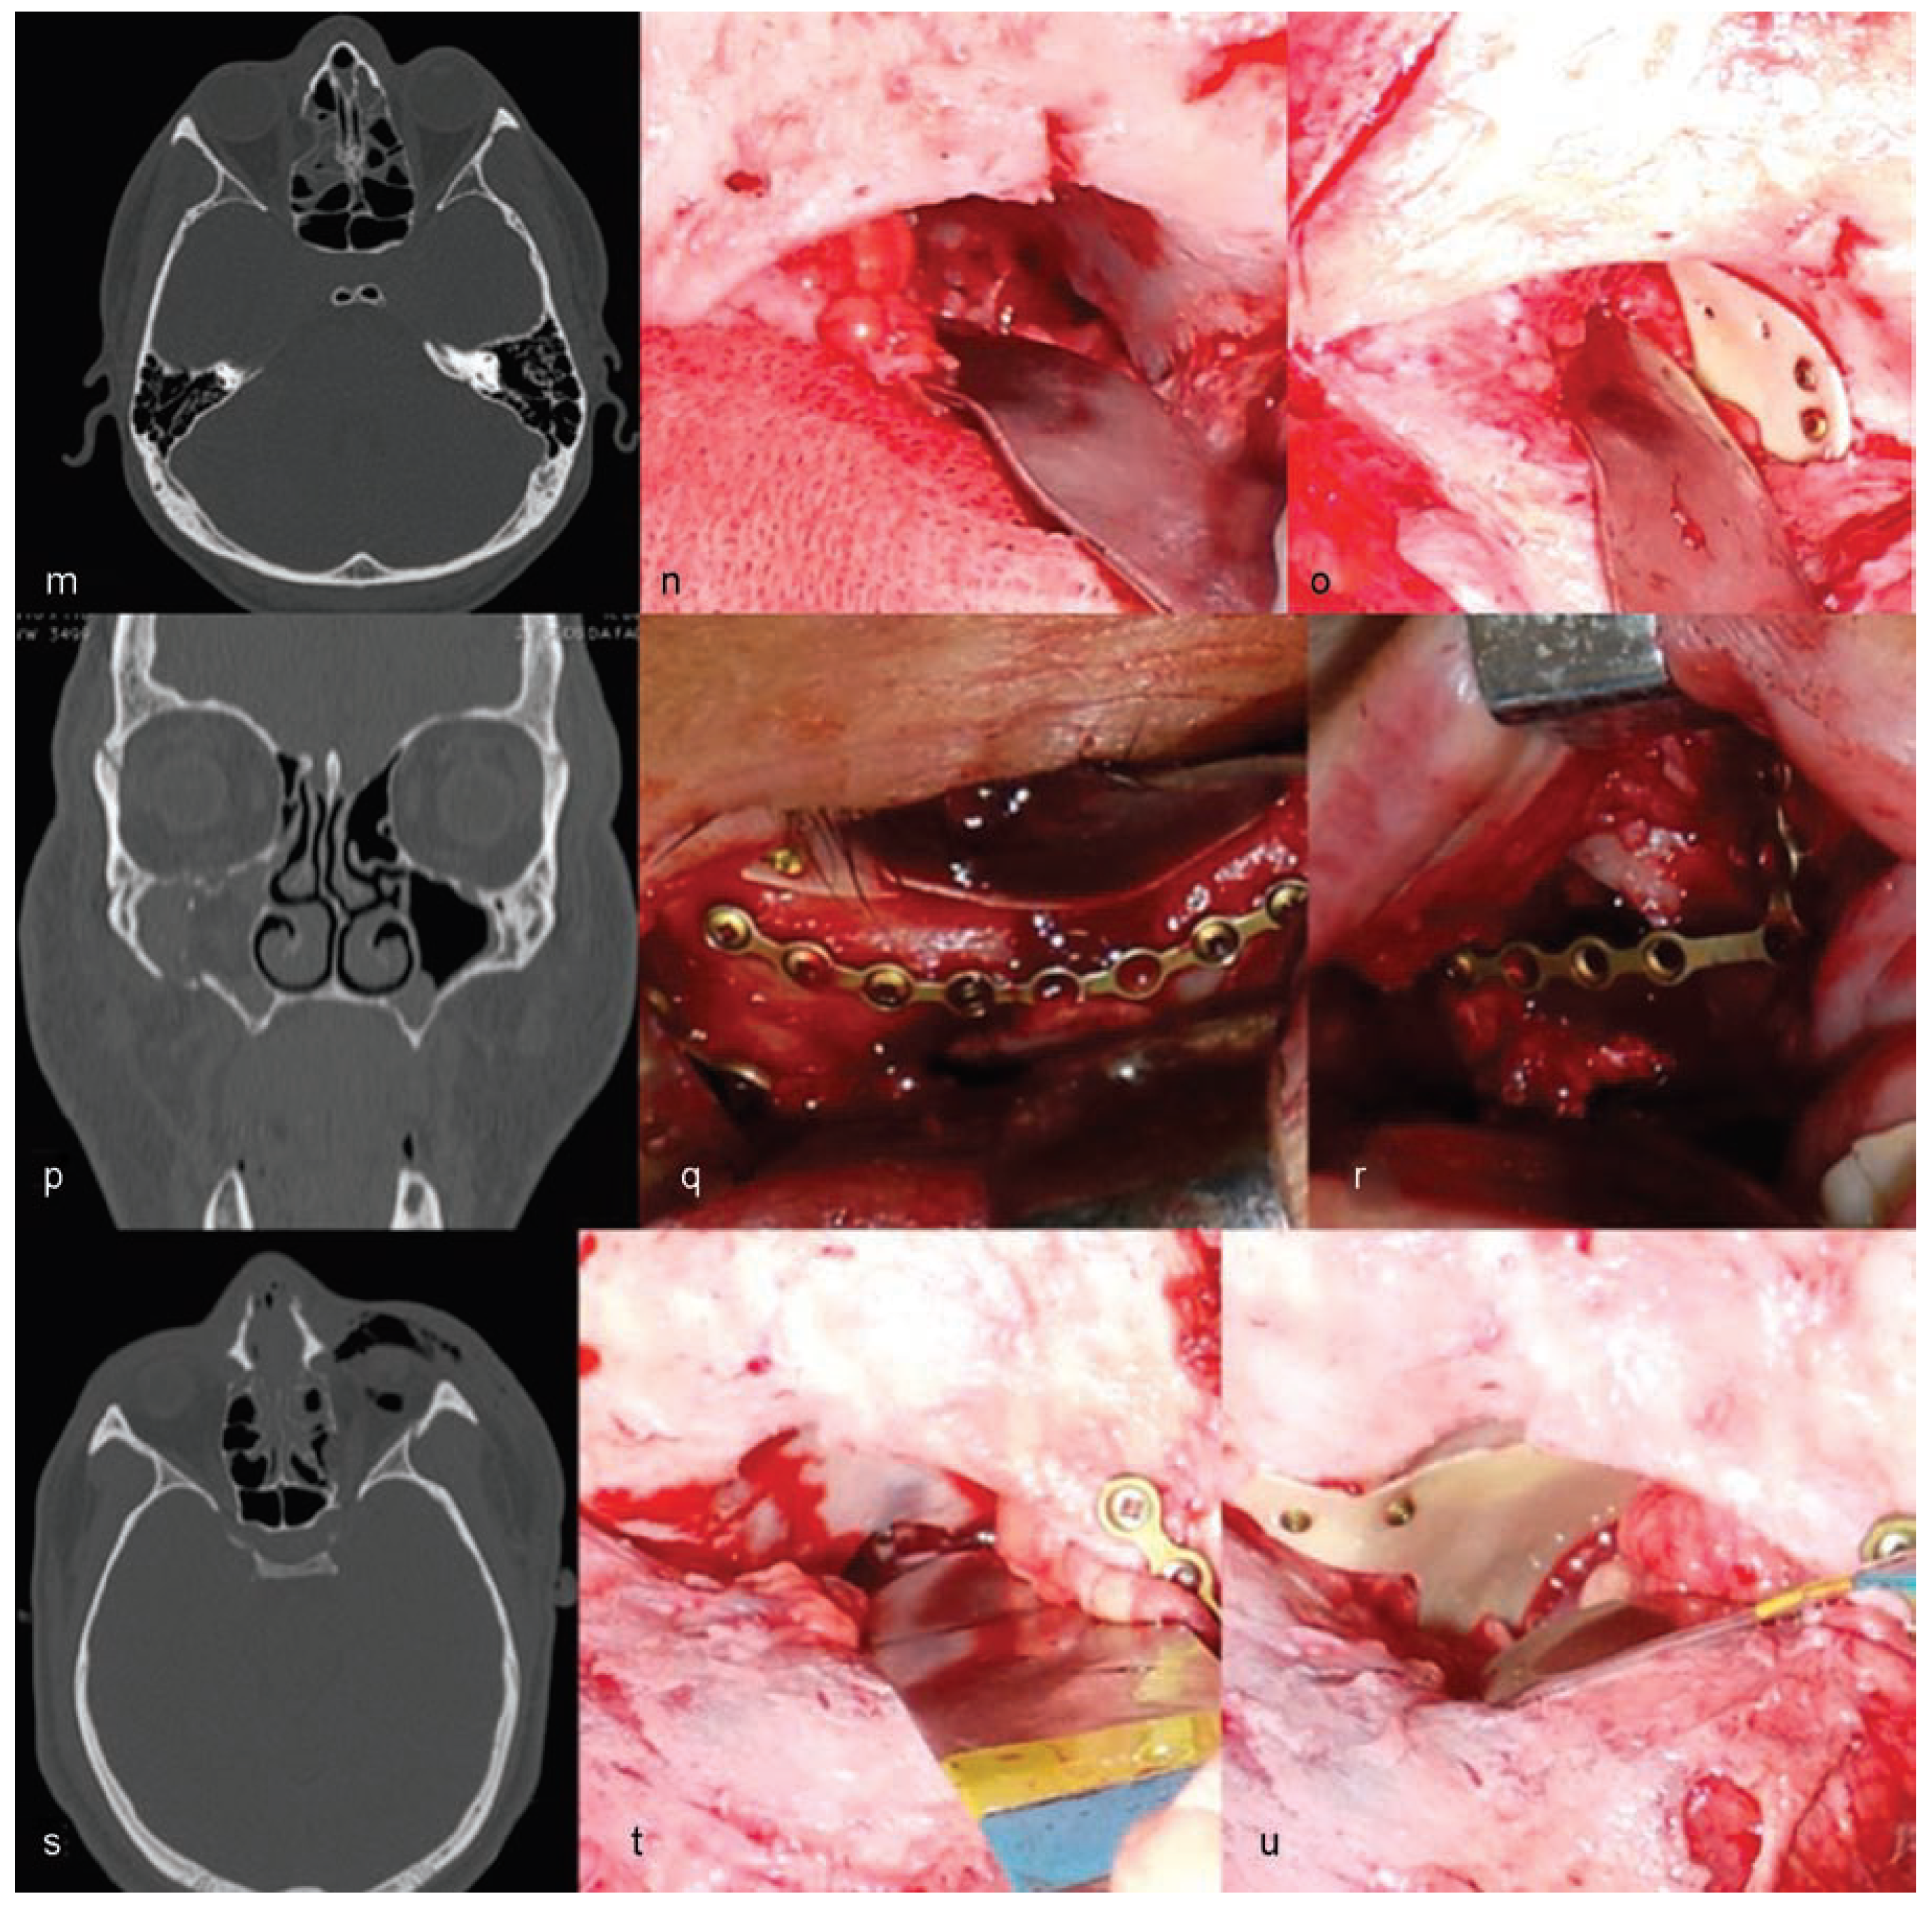

The authors are experienced with the use of castor oil polymer prostheses in several cases of trauma and surgery for camouflage deformities (Figure 1 and Figure 2).

Figure 1. Cases of patients treated with the use of castor oil polymer prosthesis I: (ac,jl) Orbital floor fractures. (di) Orbital deformity due to fibrous dysplasia.